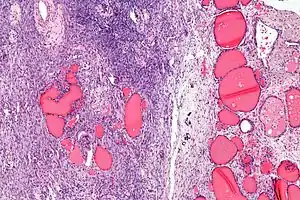

a-c)Immunohistochemical (CK19, galetin-3, HBME-1) staining of malignant struma ovarii tissues

Low magnification Struma ovarii